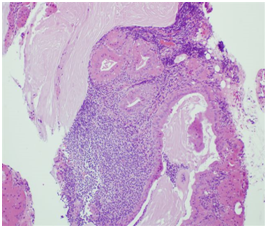

An 80-year-old Caucasian woman presented in our ENT department due to a progressive swelling on the left parotid gland during a period of two months. The physical examination showed a soft and mobile mass on the left parotid gland. The flexible fiber optic laryngoscopy showed a mass in the left laryngeal ventricle with intact laryngeal mucosa. The ultrasound of the salivary glands showed a multi - lobular tumor of both left and right parotid glands. The MRI scan showed a 1.2 x 1.1cm solid tumor in the left supraglottic region, without infiltration of adjacent tissues. In the parotid region was a 2.7 x 1.8cm solid mass in the left parotid gland as well as a 0.8 x 1.2cm solid mass in the inferior lobe of the left parotid gland (Figure 1&2). The patient was operated under general anesthesia. The larynx tumor was resected via transoral laser excision and the parotid tumor of the left side was resected via lateral parotidectomy. The histopathological examination showed a cystadenolymphoma that consist of an oncocytic epithelial cell component arranged in double layers, which develops cysts and papillary projections, and a variable amount of lymphoid tissue with germinal centers (Figure 3). An oversupply of lymphoid stroma with a characteristic formation of lymph follicles (Figure 4) was observed in all histological specimens with hematoxylin and eosin stain. There were no granulomas and no evidence of bacterial, fungal, or parasitic infection. The final diagnosis was a cystadenolymphoma in the morgagni sinus as well as multiple lesions in the parotid gland, compatible with a cystadenolymphoma. After consulting the patient, an ultrasound controlled fine needle aspiration of the tumor of the right parotid gland was performed. The histopathological examination showed a cystadenolymphoma of the right parotid gland.